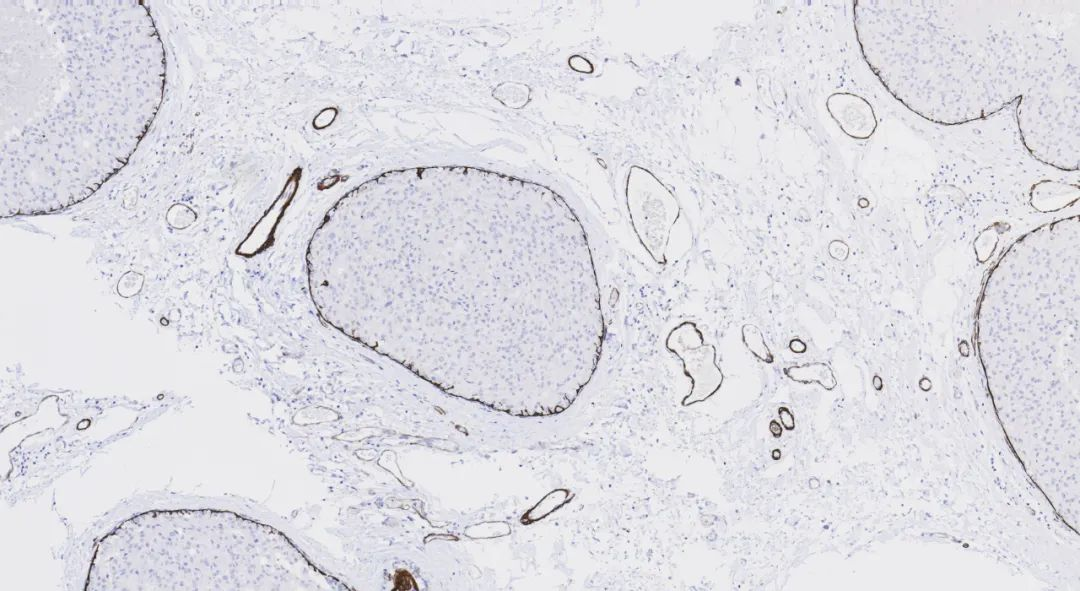

Lung adenocarcinomaFigure 2.

Napsin A (MX015) staining imageFigure 3. KidneySynaptophysin is mainly present in the presynaptic vesicle membranes of neurons, expressed in adrenal medullary cells, pancreatic islet cells, thyroid parafollicular C cells, parathyroid chief cells, skin, anterior pituitary cells, and neuroendocrine cells. It is primarily used for the diagnosis and differential diagnosis of pheochromocytoma, ganglioneuroma, paraganglioma, and tumors of the APUD system.